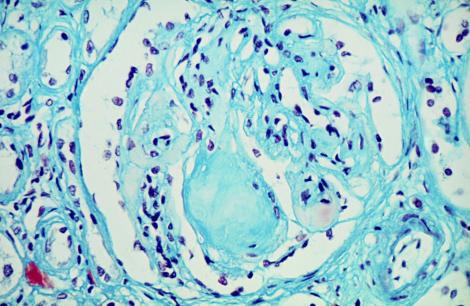

Lésions d'un glomérule rénal d'un diabétique entraînant à terme une insuffisance rénale

Crédit photo : Phanie